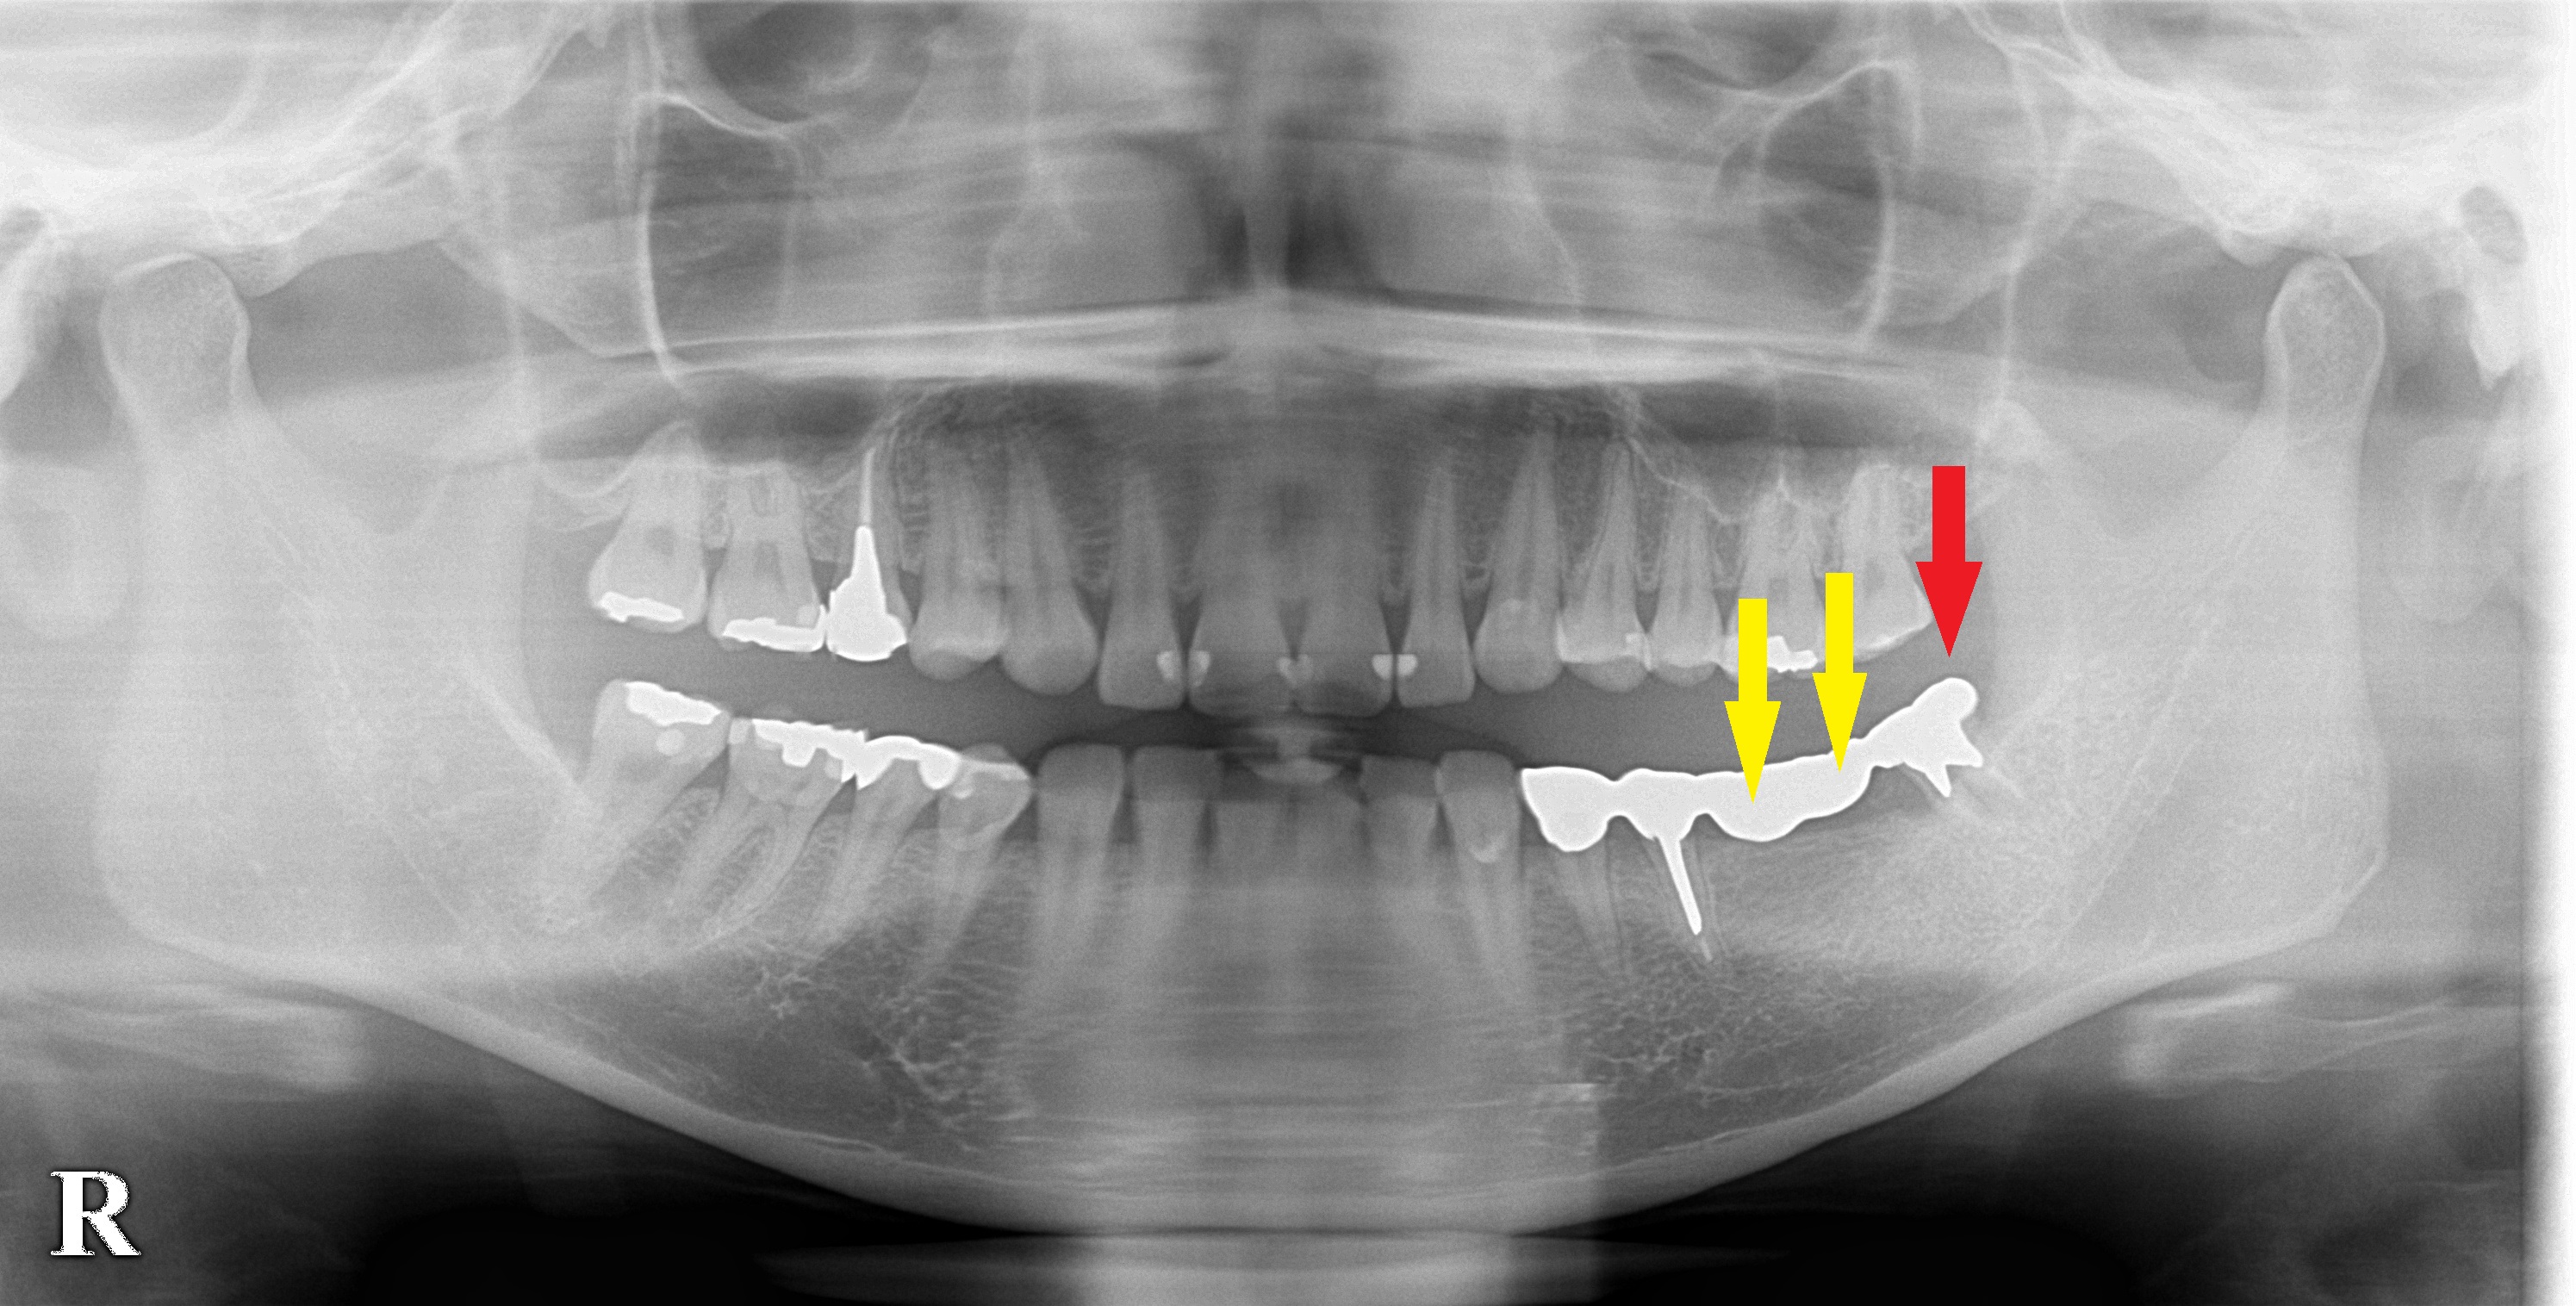

ブリッジを前方部で切断し、下の写真、赤矢印の歯を抜歯しその前方、下の写真、黄色矢印の部位に2本のインプラント埋入術を行いました。